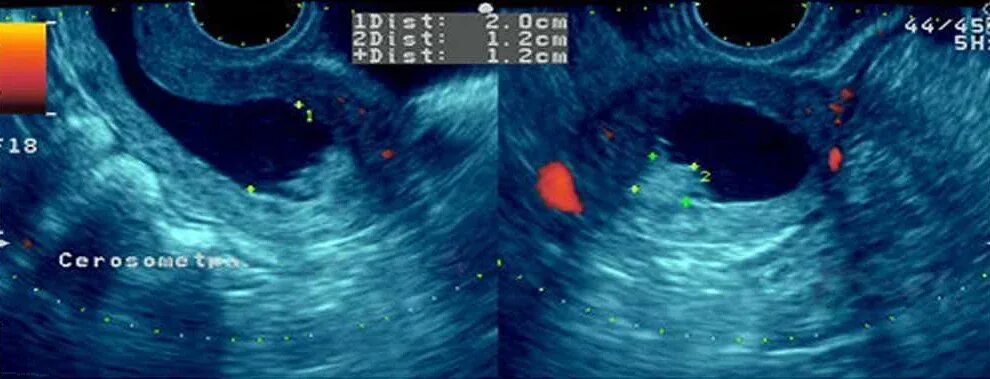

Эндометрий 11 мм